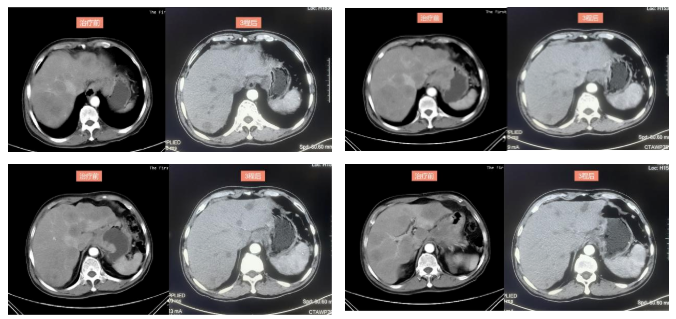

2022-4-13复查上腹部CT(3疗程后):符合贲门-胃体癌表现,伴肝内多发转移瘤,病灶均较前明显缩小,疗效评价PR。